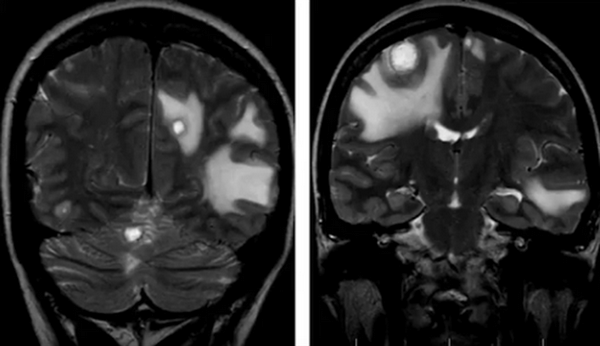

Нативная и контрастная МРТ: после усиления видны множественные мелкие метастазы головного мозга

Распознать опухоль головного мозга с помощью МРТ без контраста можно на продвинутой стадии. Малые новообразования скульптурируются значительно хуже или не видны совсем, что снижает ценность исследования. При высокой напряженности поля можно сделать нативную МРТ, снимки будут хорошего качества. Магнитно-резонансная томография выдает изображения в зависимости от запрограммированного типа сканирования, контрастирование упрощает выявление опухолей на любой стадии развития, проведение дифференциального диагноза между доброкачественным и злокачественным процессом. Побочные эффекты на введение препарата на основе хелатов гадолиния развиваются крайне редко, меньше чем у 1% людей. При наличии показаний отказываться от контрастного усиления не стоит. Пациентам, страдающим почечной или печеночной недостаточностью в декомпенсированной стадии, может быть выполнена обычная МРТ. Магнитно-резонансное сканирование без динамического контрастирования на томографе с небольшой мощностью обнаружит объемное поражение головного мозга значительных размеров. После внутривенного введения парамагнетика можно более точно определить локализацию, объем, степень инвазии, рассмотреть кровоснабжение опухоли, оценить индивидуальные особенности, что имеет значение для планирования лечения.

До- и постконтрастное изображение злокачественной опухоли головного мозга